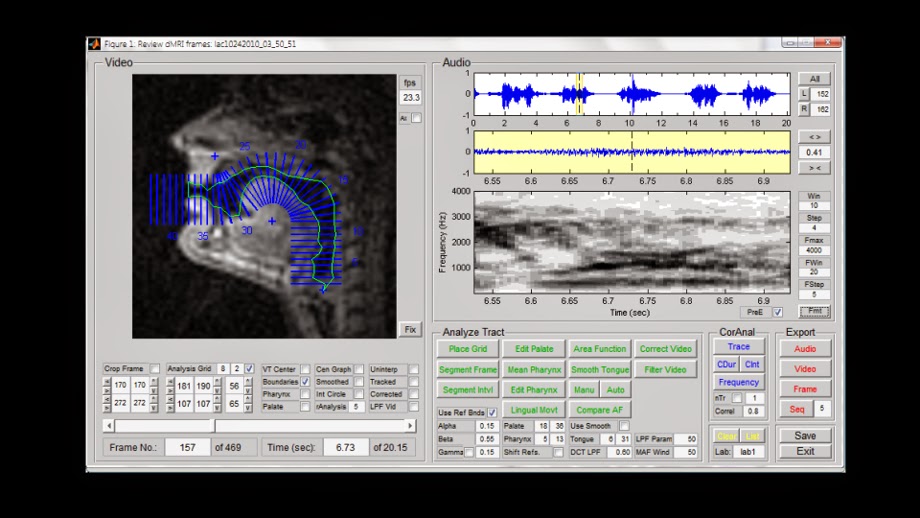

Investigadores del Laboratorio de Análisis e Interpretación de Señales de la Universidad del Sur de California utilizaron imágenes de resonancia magnética (MRI) para examinar qué «mecanismos paralingüísticos» utilizan los beatboxers.

El equipo mostró el interés de un escaneo de resonancia magnética (MRI) en tiempo real para observar los tractos vocales de los beatboxers, justo antes de que emitieran un sonido para ver si esos movimientos son diferentes del habla.

Los videos de resonancia magnética de las actuaciones se combinaron con sus voces grabadas y los diversos efectos que crearon se analizaron para descubrir cómo la boca del artista realmente podía hacer cada sonido.

Los resultados en tiempo real proporcionaron una visión dinámica de todo el tracto vocal medio sagital y a una frecuencia de cuadro lo suficientemente alta como para observar el movimiento y la coordinación de los articuladores críticos.